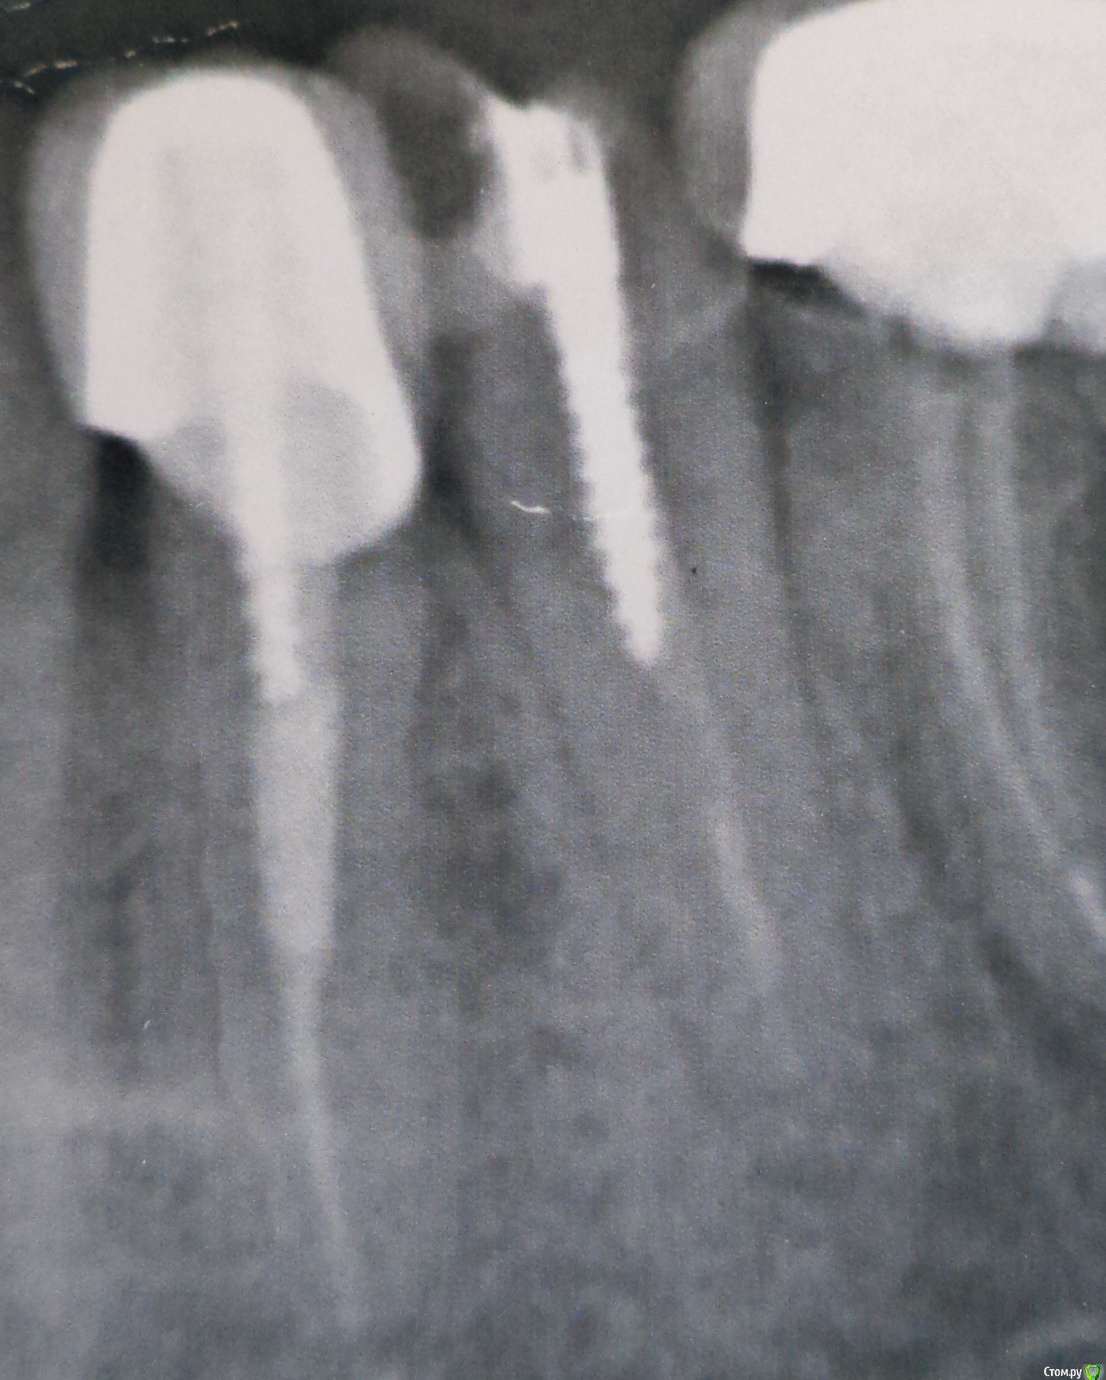

полосатая Опубликовано 15 декабря, 2016 Поделиться Опубликовано 15 декабря, 2016 Здравствуйте. Раньше в пятерке стоял штифт и фотополимерная пломба. Зуб не болел, но учитывая давность лечения , да штифт стал просвечивать через пломбу, я попросила перелечить этот зуб.Штифт был удален с ультразвуком, положили кальций на пару недель под временную пломбу.Зуб стал чувствительным при постукивании. На снимке вроде бы все нормально.Врач предположила перелом корня...и положила в канал кальций с йодоформом + трихопол. Зуб стал болеть, появился отек и припухлость. Я предупреждала о том, что аллергии на йод у меня нет, но йодоформ у меня всегда вызывает обострения с гноем и отеком. Но она настояла та том что "лучше пусть будет обострение, чтобы с гноем все вышло".У меня вопрос: применение йода и вызывание обострения - это обязательно при эндодонтическом лечении? Насколько это оправдано при переломах корней? Ссылка на комментарий

DmitrySH Опубликовано 15 декабря, 2016 Поделиться Опубликовано 15 декабря, 2016 (изменено) По этому снимку сложно что-то сказать про трещину. Трещина обычно выявляется при визуальном осмотре. На снимках она видна когда зуб совсем развалился. Изменено 15 декабря, 2016 пользователем DmitrySH 1 Ссылка на комментарий

red_butler Опубликовано 15 декабря, 2016 Поделиться Опубликовано 15 декабря, 2016 Думается мне йодоформ не при чем. На снимках перелома, или того что свидетельствовало бы о его наличии не увидел. Нужно смотреть очно. Ищите врача. Ссылка на комментарий